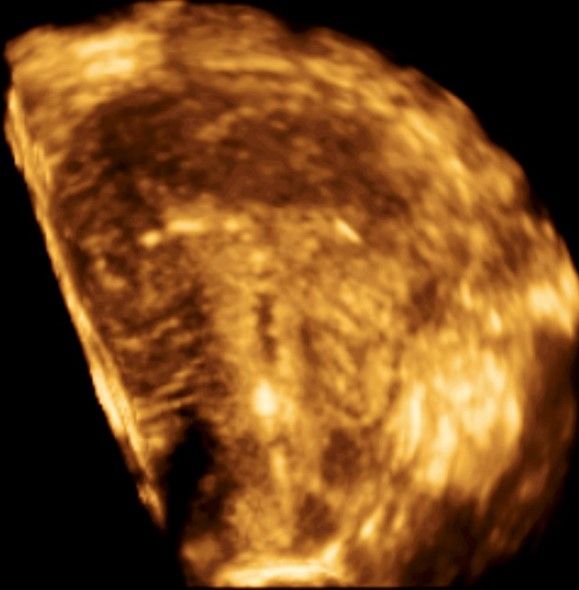

Современные экспертные УЗИ сканеры дают возможность проводить исследования всех органов в 3D. Это позволяет, используя полученный массив данных, получать диагностические сечения в любой плоскости, недоступной для обычного 2D УЗИ. Наиболее интересной является фронтальная. Например, визуализация полости матки. Диагностическая возможность выявления пороков развития превосходит все другие методы (рентгеновские и МРТ). Метод также позволяет уточнить положение ВМК (спирали) в полости матки, расположение миоматозных узлов, расположение плодного яйца на малых сроках, полипов. Сегодня современное экспертное ультразвуковое исследование невозможно без использования 3D УЗИ.